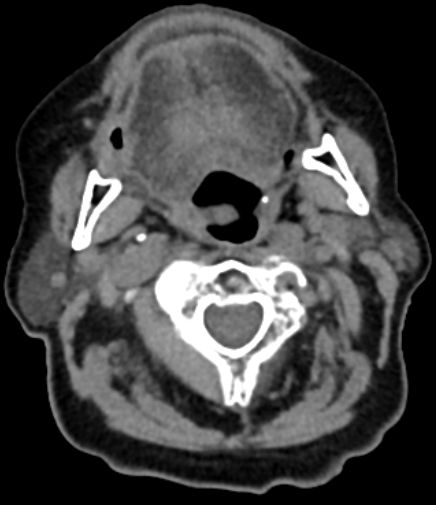

63-jähriger Mann mit Leberzirrhose und ACI-Stenose.

Es besteht ein Hypopharynx - Karzinom und ein Weichgaumenkarzinom mit Übergang auf den harten Gaumen.![]() | |||||||||||||||||